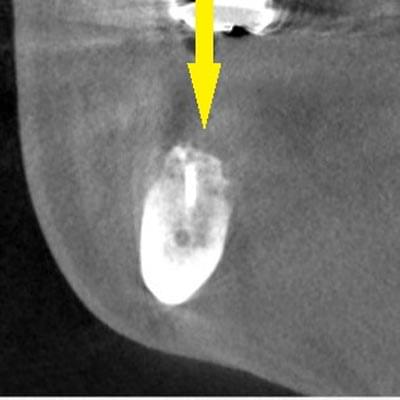

CTで見ると、骨が薄いのが良く分かります。黄色の矢印の部分、白く写るのが骨で、矢印のある黒い部分が上顎洞という空洞です。

サイナスリフトによる骨造成について

この空洞部分に、人工骨を入れて、閉鎖しておくと、数か月ほどで骨に置き代わっていき、インプラントを埋入できるだけの骨量になります。サイナスリフトが終了して、数か月経過し、薄かった骨が十分な厚みができたCT画像です。黄色矢印の部分、白く写る骨が増えています。